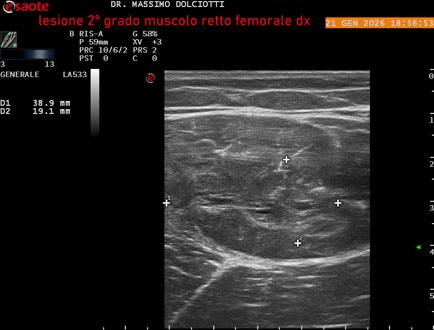

Data inserimento: 23/01/2026

Ecografia del: 21/01/2025

Strumento: Esaote MyLab Eight

Sonda: Lineare Multifrequenza 3-13 MHz

Età Paziente: M 23 anni

Motivazione dell'esame: dolore al terzo prossimale della coscia destra da tre giornii.

Commento all'esame: le immagini ed il video documentano, al terzo prossimale del muscolo retto femorale destro, area disomogenea, ipoecogena, delle dimensioni di 35 mm per uno spessore di 18 mm, misura ottenuta per asse corto o trasversale, e di 71 mm x 20 mm, misura ottenuta per asse lungo o longitudinale, da ricondurre a lesione muscolare di 2° grado con modica raccolta sieroematica intramuscolare.

Conclusioni: lesione di 2° grado del muscolo retto femorale destro (2nd degree injury of the right rectus femoris muscle).